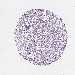

PANCREATIC CANCER - Protein expressioni

A mouse-over function shows sample information and annotation data. Click on an image to view it in a full screen mode. Samples can be filtered based on level of antibody staining by selecting one or several of the following categories: high, medium, low and not detected. The assay and annotation is described here.

Note that samples used for immunohistochemistry by the Human Protein Atlas do not correspond to samples in the TCGA dataset.

Antibody stainingi

Antibody staining in the annotated cell types in the current human tissue is reported as not detected, low, medium, or high, based on conventional immunohistochemistry profiling in selected tissues. This score is based on the combination of the staining intensity and fraction of stained cells.

Each image is clickable and will lead to virtual microscopy that enables deeper exploration of all samples and also displays staining intensity scores, fraction scores and subcellular localization as well as patient and tissue information for each sample.

Antibody HPA067203

Antibody CAB025507

Antibody CAB073546

Staining

High

Medium

Low

Not detected

Intensity

Strong

Moderate

Weak

Negative

Quantity

>75%

75%-25%

<25%

None

Location

Nuclear

Cytoplasmic/membranous

Cytoplasmic/membranous,nuclear

Adenocarcinoma, NOS